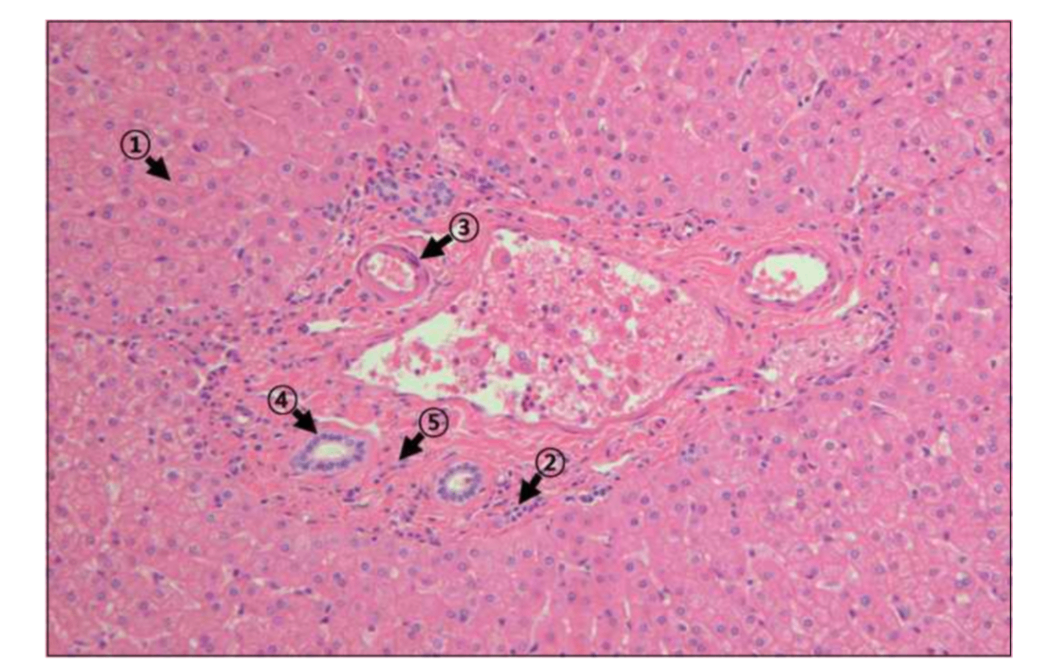

25세 남자(기부자)는 간경변으로 고생하는 아버지의 생체 간 이식을 위해 본인의 간 일부를 제공하였다. 이 기부자의 간은 거의 정상 크기로 재생할 것으로 예상된다. 이때 활발한 세포 분열을 통하여 간의 재생에 가장 많이 기여하는 세포는?

• 간 재생은 간세포의 활발한 분열과 증식에 의해 이루어진다.